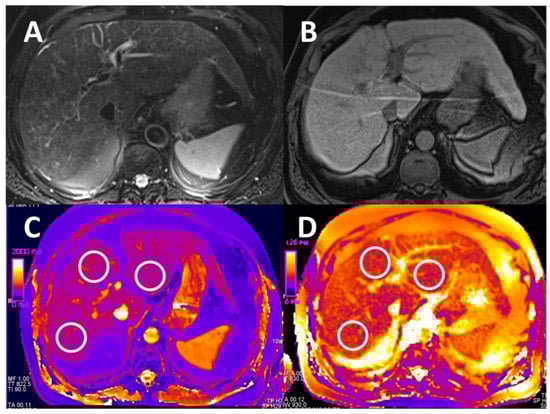

2.4. Image Analysis

2.4.1. T1 and T2 Relaxometry